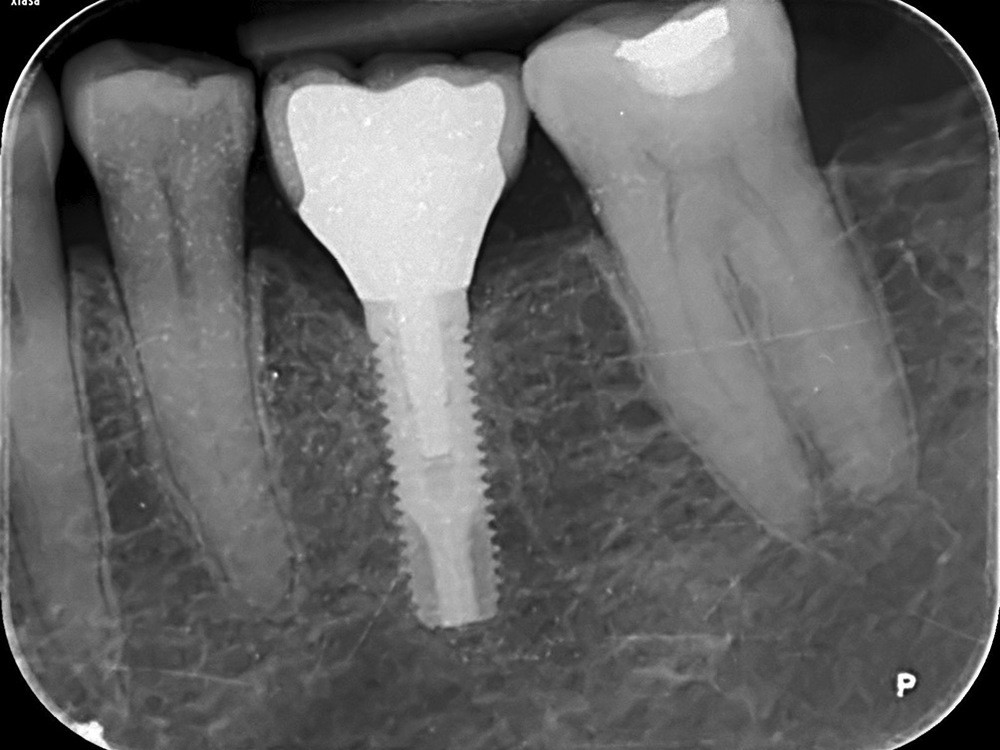

– la péri-implantite définie comme une inflammation des tissus mous péri-implantaires avec une destruction irréversible de l’os péri-implantaire (fig. 2a-b).